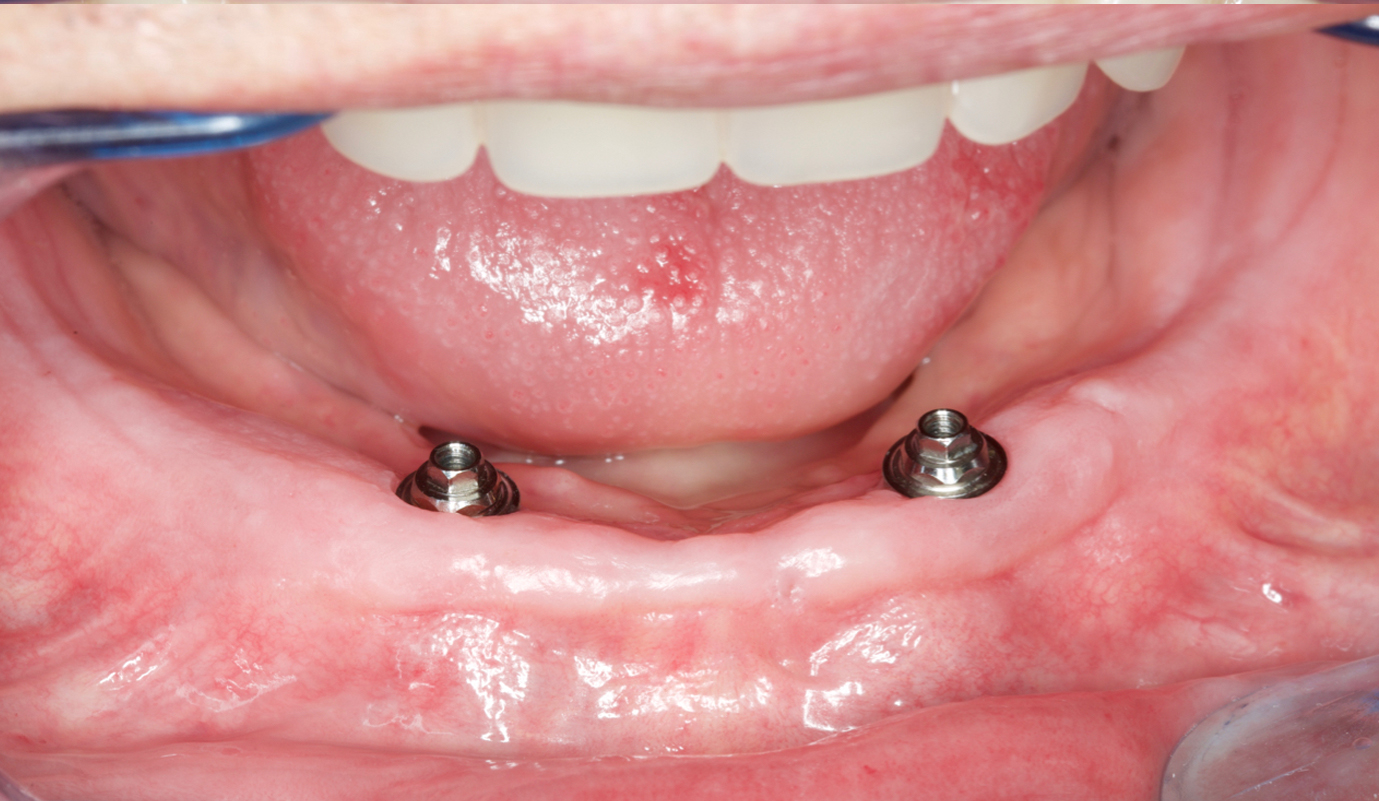

Utilizadas para a substituição de alguns ou de todos os dentes, podem ser ajustadas e apoiadas nas estruturas naturais (gengiva e dentes) ou apoiadas em implantes osteointegrados.

A colocação de implantes revolucionou o tratamento destes pacientes, permitindo a reabilitação com próteses fixas ou removíveis estabilizadas, mas mantendo os princípios clássicos de reabilitação.

Casos de próteses sobre implantes